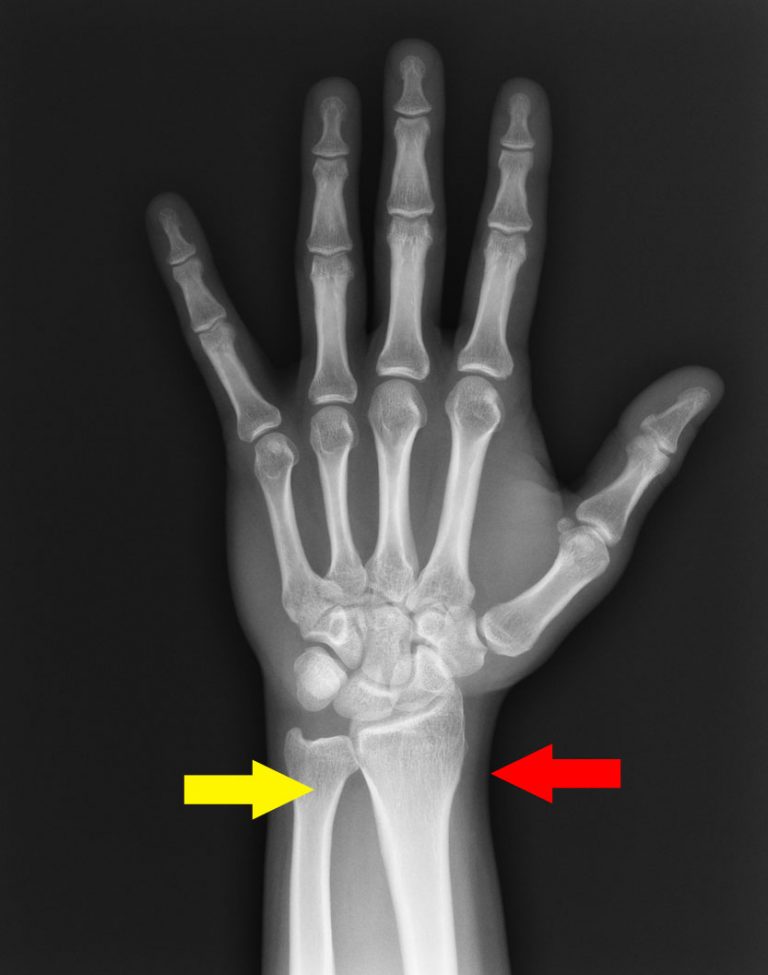

Fork Break Wrist . when the radius breaks near the wrist, it is called a distal radius fracture. displaced fractures usually present with a 'dinner fork' deformity and require closed reduction and possible. A colles fracture is a complete fracture of the radius bone of the forearm close to the wrist resulting in an upward (posterior). Deformity of the wrist, sometimes called a “dinner fork deformity,” which causes it to look. a dinner fork deformity, also known as a bayonet deformity, occurs as the result of a malunited distal radial fracture, usually a colles fracture. a distal radius fracture, also known as wrist fracture, is a break of the part of the radius bone which is close to the wrist. The break usually happens due to falling on an outstretched or flexed hand.

A colles fracture is a complete fracture of the radius bone of the forearm close to the wrist resulting in an upward (posterior). a distal radius fracture, also known as wrist fracture, is a break of the part of the radius bone which is close to the wrist. The break usually happens due to falling on an outstretched or flexed hand. displaced fractures usually present with a 'dinner fork' deformity and require closed reduction and possible. when the radius breaks near the wrist, it is called a distal radius fracture. Deformity of the wrist, sometimes called a “dinner fork deformity,” which causes it to look. a dinner fork deformity, also known as a bayonet deformity, occurs as the result of a malunited distal radial fracture, usually a colles fracture.

Fork Break Wrist a dinner fork deformity, also known as a bayonet deformity, occurs as the result of a malunited distal radial fracture, usually a colles fracture. when the radius breaks near the wrist, it is called a distal radius fracture. A colles fracture is a complete fracture of the radius bone of the forearm close to the wrist resulting in an upward (posterior). displaced fractures usually present with a 'dinner fork' deformity and require closed reduction and possible. The break usually happens due to falling on an outstretched or flexed hand. a distal radius fracture, also known as wrist fracture, is a break of the part of the radius bone which is close to the wrist. Deformity of the wrist, sometimes called a “dinner fork deformity,” which causes it to look. a dinner fork deformity, also known as a bayonet deformity, occurs as the result of a malunited distal radial fracture, usually a colles fracture.